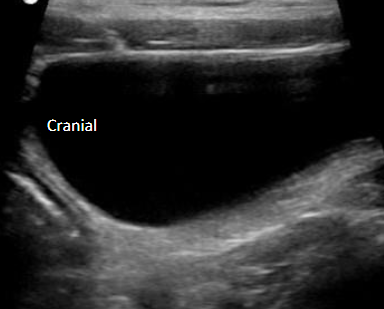

Abdominal ultrasound is a non-invasive, pain-free imaging tool that allows our veterinarians to see inside your pet’s abdomen in real time — helping us assess organs such as the liver, kidneys, spleen, bladder, and intestines with incredible detail.